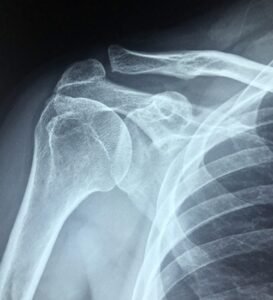

Frozen shoulder, also called adhesive capsulitis, is a painful and disabling condition where the shoulder joint becomes stiff and movement is restricted. Many people search for “frozen shoulder treatment near me” when this problem starts interfering with daily life.

Frozen shoulder develops when the capsule around the shoulder joint thickens and tightens, leading to stiffness and pain. It usually progresses in stages and may last for months if not treated.